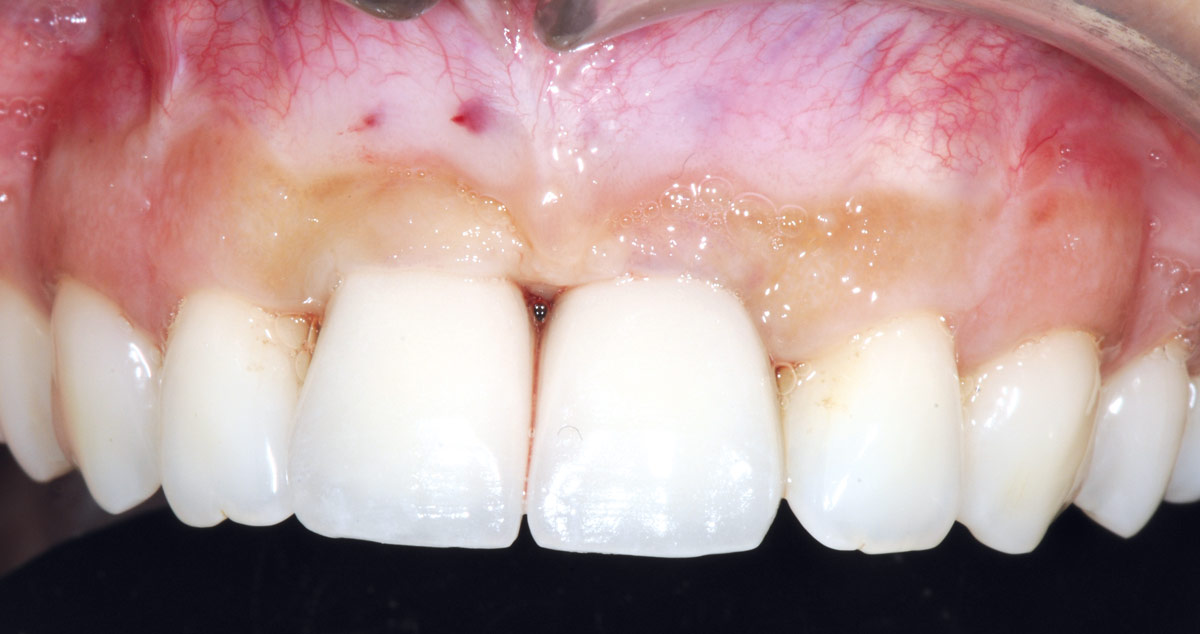

21/26 - 6 months after surgery: healthy soft tissuesBone augmentation in aesthetic zone with maxgraft® bonering - Dr. A. Patel